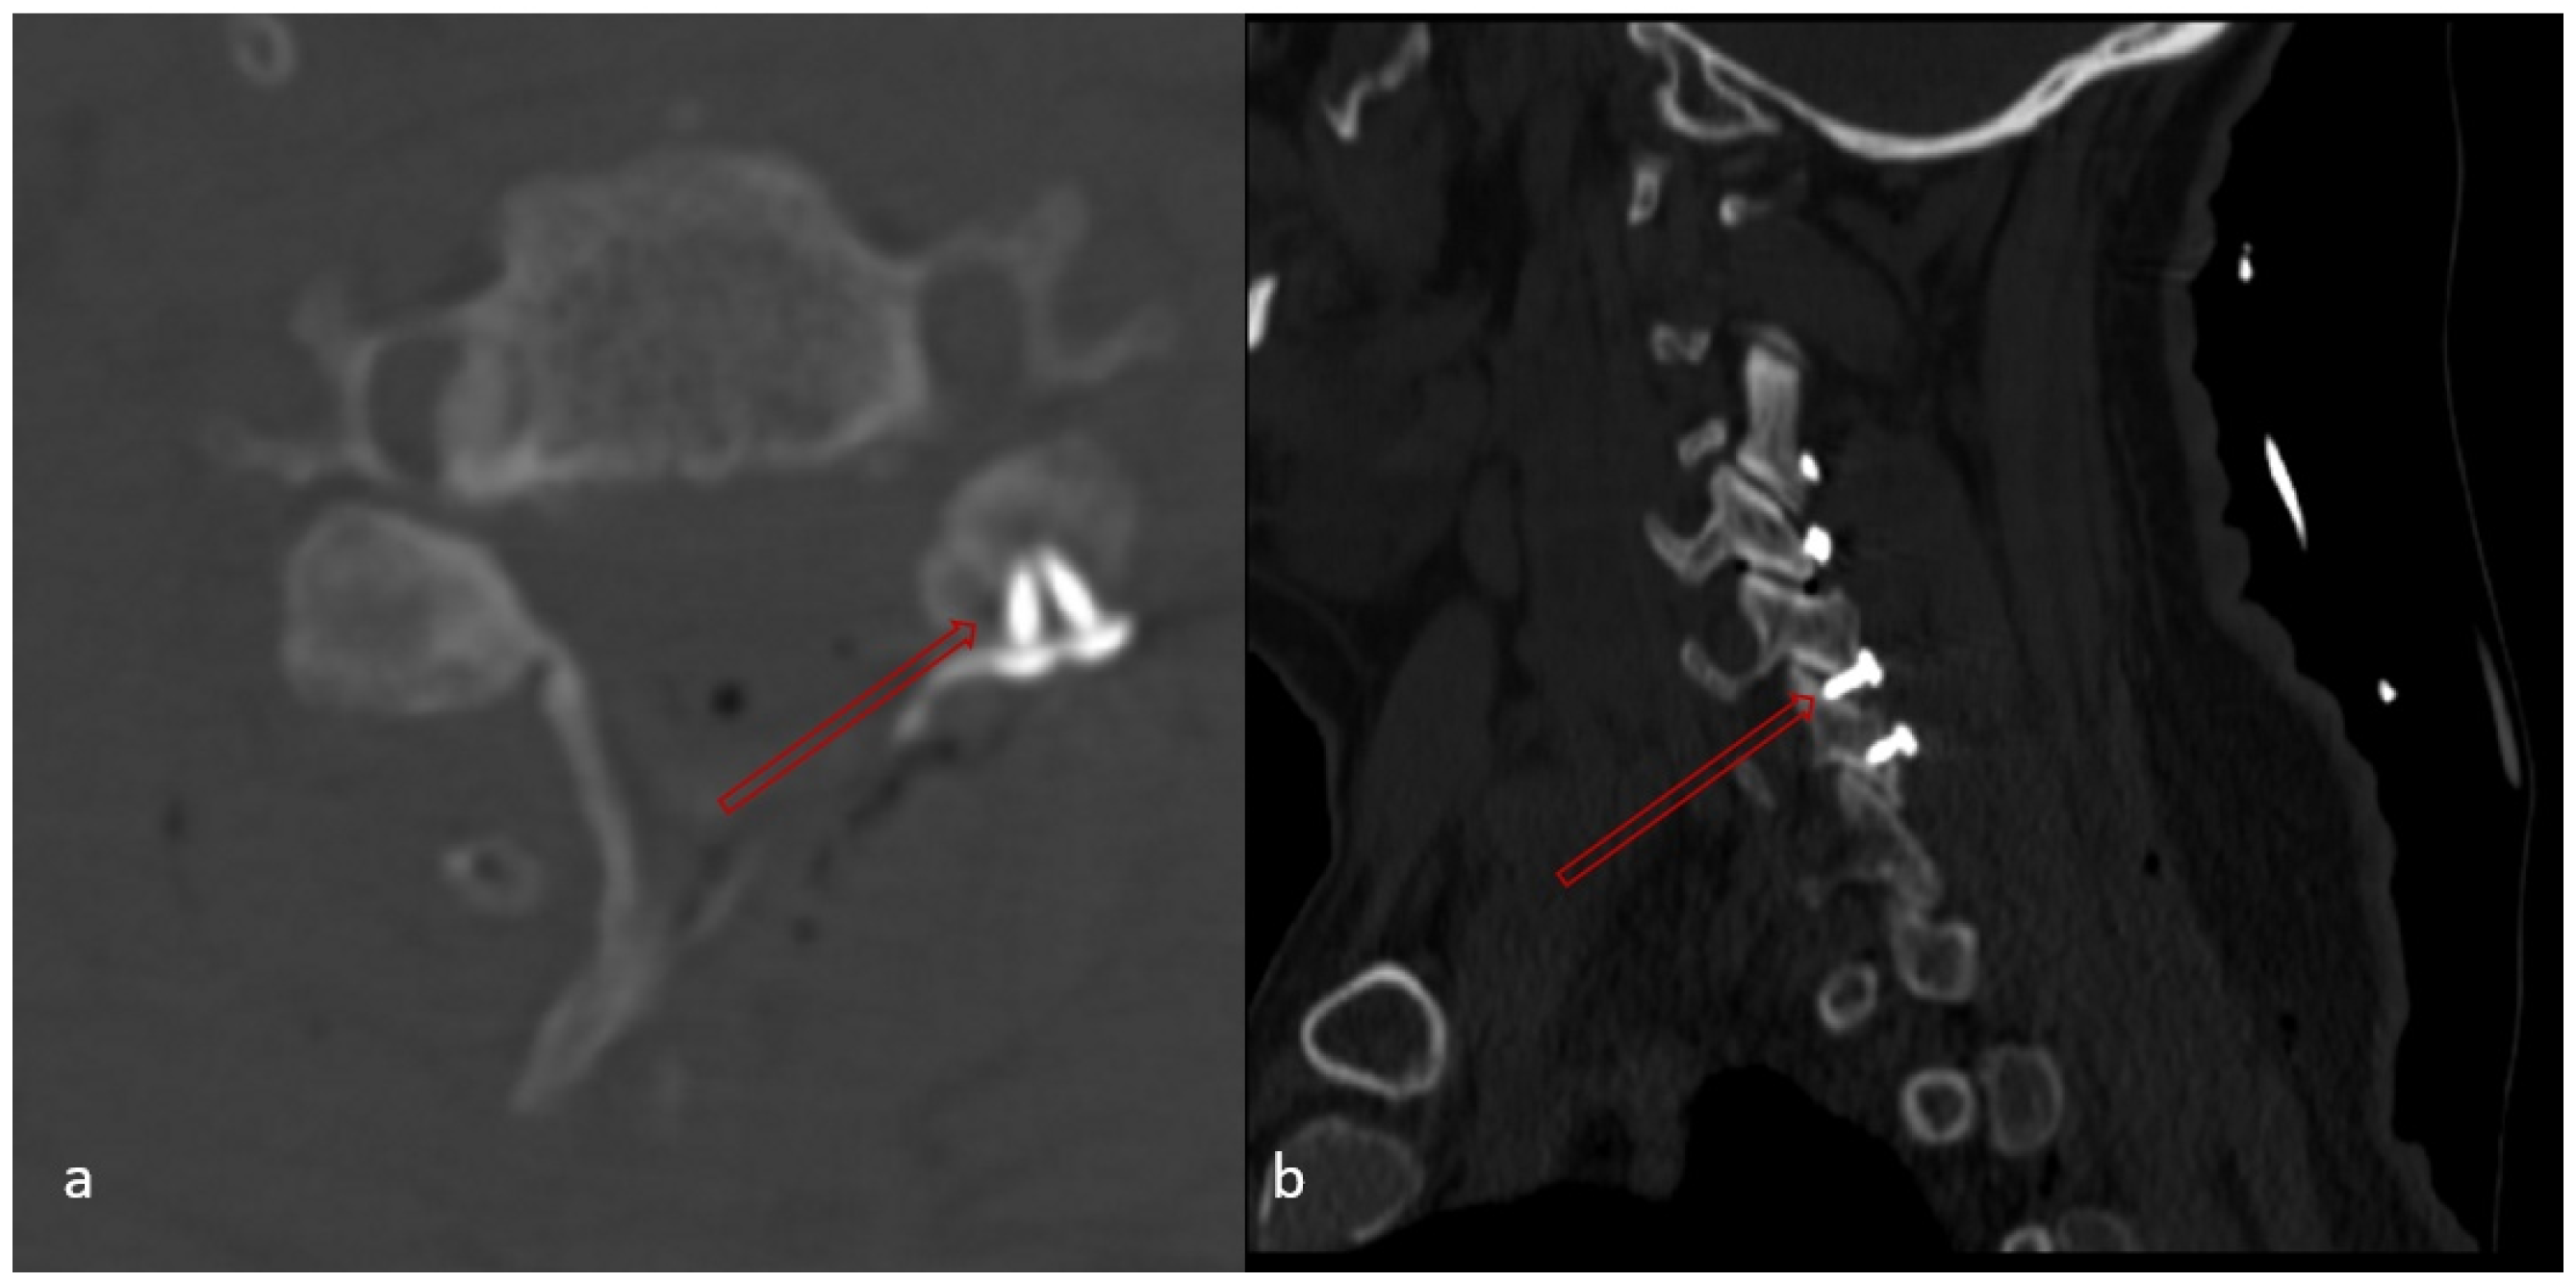

- Whether any of the screw placed in the lateral mass causes facet joint disturbance or not (Figure 6),

- Number of facet disturbance,

- Whether there is uppermost facet disturbance or not,

- Whether there is lowermost facet disturbance or not